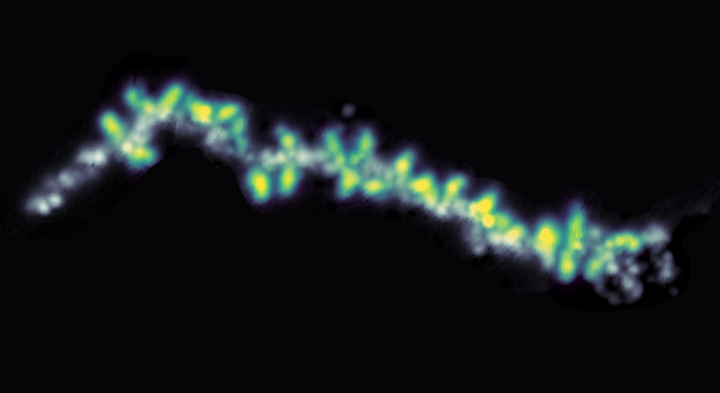

Det laver et nyt studie om på. Med en banebrydende ny teknologi har forskere fra Københavns Universitet og Max Planck Instituttet taget det første billede af et protein med sukkermolekyler på.

"En avanceret mikroskopiteknik giver os mulighed for at visualisere glykoproteiner med fuld struktur af proteinrygraden og glykan knyttet til proteinet," siger lektor Rebecca Miller fra Copenhagen Center for Glycomics ved Institut for Cellulær og Molekylær Medicin.

"De fleste teknikker til at studere proteiner formår ikke at visualisere glykaner. Men med vores nye undersøgelse viser vi, at det er muligt,” siger Rebecca Miller.

Elektrospray Ion Beam Deposition Scanning Tunneling Mikroskopi Teknologien bag det nye studie hedder Electrospray Ion Beam Deposition Scanning Tunneling Microscopy (ESIBD-STM). Det er placeret på Max Planck Institute og er en ny kombination af eksisterende teknologier. Grundlæggende er det massespektrometri kombineret med avanceret mikroskopi. |